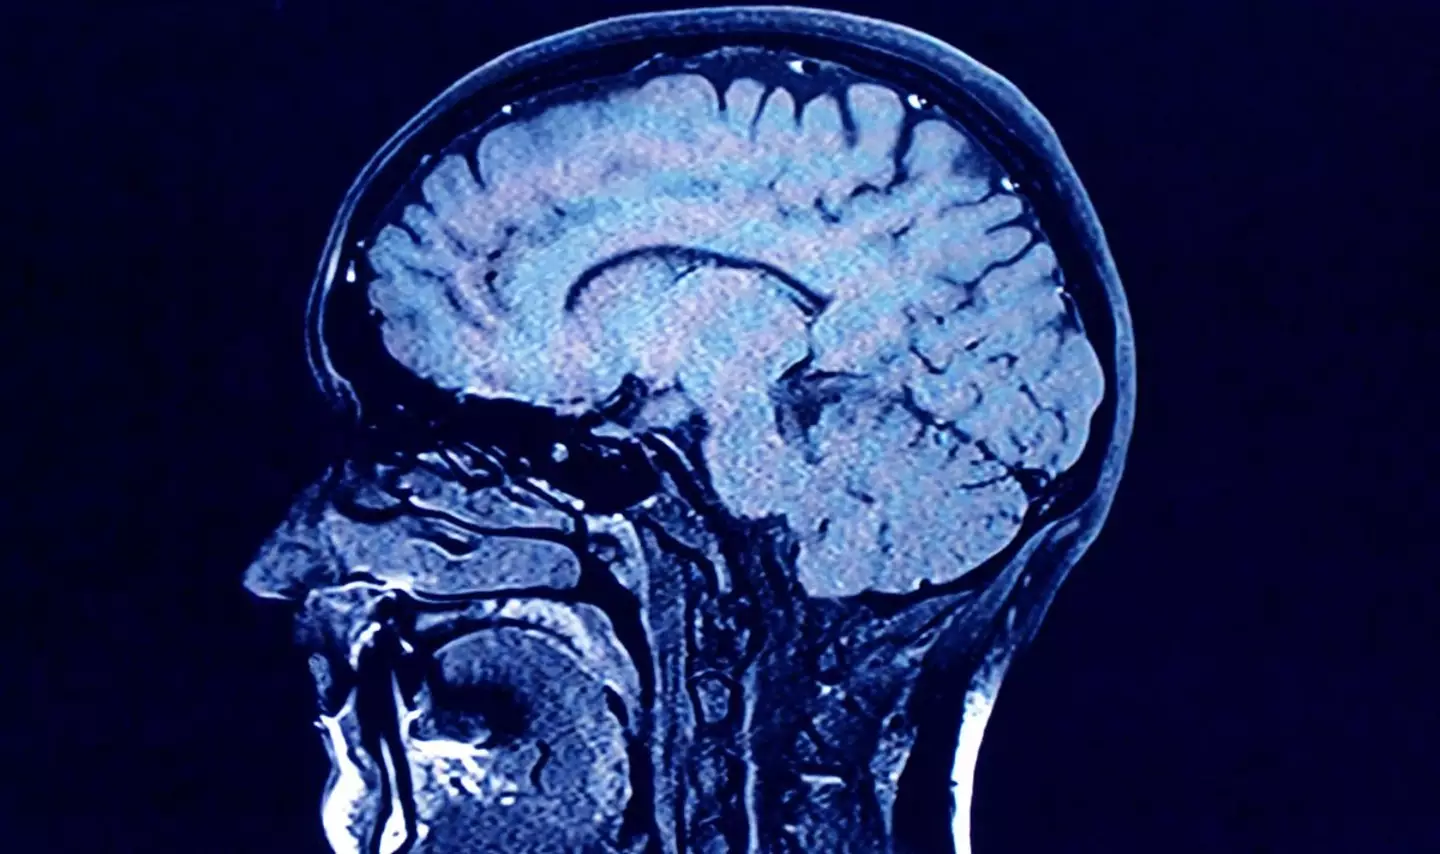

“Sensitive people have empathy in spades, so much so that the difference can be seen in brain scans,” said Sensitive authors Jenn Granneman and Andre Solo.